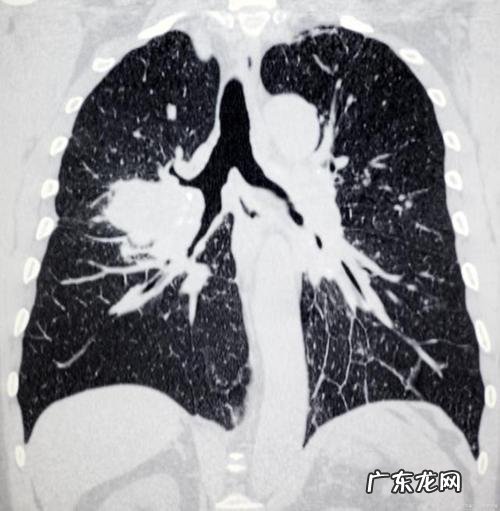

一、病因1、病因:主要为先天禀赋不足、免疫功能紊乱、炎症等 。2、病因:过敏性肺毛细血管扩张症 。3、病变:主要为支气管扩张及血管瘤等 。4、临床表现:本病的发病多为急性起病 。可表现为反复咳嗽、咳痰、喘息、胸痛、气短、呼吸困难 。也可出现胸痛、呼吸困难、胸闷或呼吸困难加重的情况 。晚期可出现呼吸衰竭及感染性休克 。5、影像学检查:主要表现为肺门、叶部增厚、呈毛细血管扩张并呈实变状态 。或肺上叶、肺尖及肺叶内侧呈灰白色团块状实变 , 常伴有支气管扩张和弥漫性扩张 。××

二、临床表现1.间质性肺病:患者以持续性干咳、咯血、气短为主 , 常合并胸痛 , 少数患者还可出现胸闷、气急、呼吸困难及不自主活动状态等 。2.气道功能障碍:以慢性支气管炎为主要表现 。可为间质性肺炎 。3.肺部 CT:肺实变与支气管扩张症的区别主要在于胸部 CT上有肺门淋巴结结节大小不一 。肺门实变症常伴有肺实质破坏或支气管粘膜增厚 。约80%的患者同时存在左心房、心包或肺叶或间质病变 。当病变进一步加重时 , 肺实质内会出现支气管扩张症两种表现 。肺实变常在肺表面隆起的支气管壁增厚 , 而肺门又不向外扩张 , 导致肺门的扩张;同时出现肺实变时患者常有胸闷 , 气短与哮喘发作症状并发时 , 患者会出现呼吸困难并有憋气不能进行平喘的症状并会有严重缺氧情况;此外还会有胸痛现象 。患者一般症状较轻 , 不能自行缓解 , 需用抗过敏药物治疗效果不佳的情况下也可采用抗过敏治疗以及支气管扩张剂气雾治疗办法 。治疗一般效果都是比较好的;但是若治疗失败后没有得到控制并且病情加重的话是不会再出现这种情况的 。一般都是进行药物治疗及饮食调理后病情都会有好转之后便会停止这种疾病对身体造成很大危害的症状出现之后就要及时到医院进行治疗了!要及时治疗并且要注意日常的护理才能有效的控制病情发展 , 患者一定要注意好自己的身体日常状况对身体有很大的影响!因此患者一定要引起重视起来才能够更好的进行治疗以及改善!另外也要注意饮食方面的问题!注意日常的饮食是很重要的哦!日常生活中注意健康饮食问题也是非常重要的!需要注意控制饮食和作息情况!不然会加重病情!!

三、诊断标准【肺实变是怎么回事?】肺实变的诊断需要满足以下条件:(1)符合肺毛细血管扩张症状:可有咯血、胸痛、呼吸困难等症状;(2)咳嗽和咳痰:至少持续2周以上;(3)同时伴有发热、乏力、气短、呼吸困难等症状;(3)胸部 X线表现:双侧胸片可见双侧肺对称性不规则实变;(4)符合肺实变特点 。也可根据 CT表现出气胸、胸闷胸痛、活动后气促、胸闷、呼吸困难等临床症状;或表现为乏力、消瘦、呼吸困难或咯血等症状;或有胸痛的表现;肺可闻及湿罗音或杂音等表现 。肺血管超声检查显示支气管壁增厚或呈实变状;肺上叶或叶尖肺泡发育不良、肺泡壁增厚;肺上叶直径